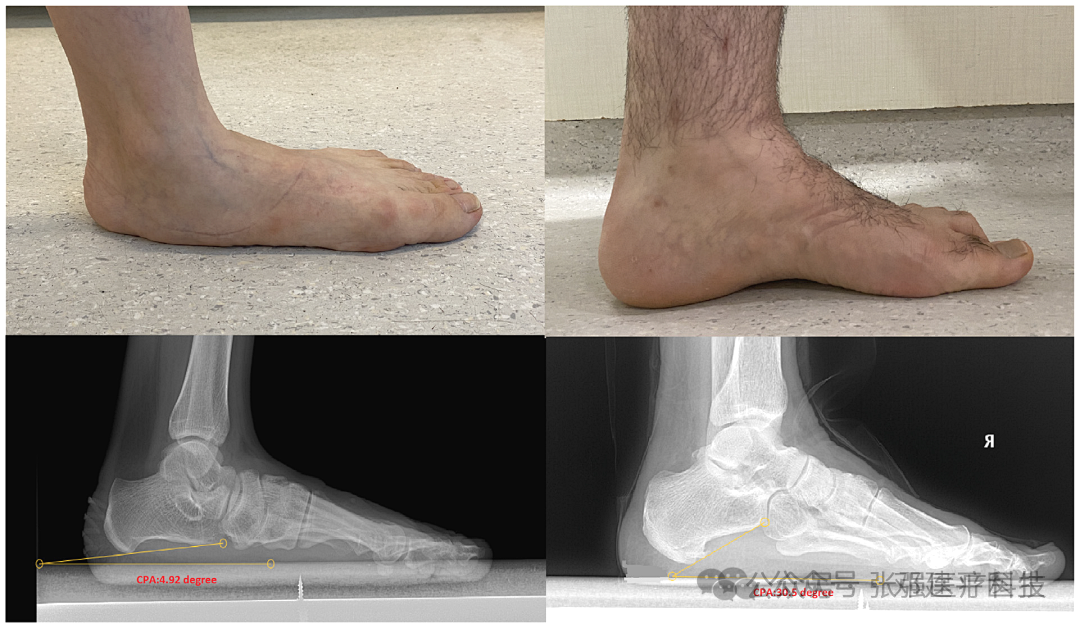

有研究报道,大约 27% 的成年人患有 CVD,CVD 的病因涉及年龄、性别、静脉曲张家族史、肥胖、妊娠、静脉炎、腿部受伤史以及环境或行为因素(例如长时间站立和坐着)等因素。 静态足部疾病 (SFD),主要包括扁平足和高足弓。

可能是先天发育异常,也可能是成年后获得的。年龄增长、肥胖、韧带松弛、创伤和全身炎症是常见原因。

SFD的主要症状为脚内侧足弓疼痛和由于姿势障碍引起的腿部疼痛。 SFD看似是足部的局部问题,却可能与静脉曲张有着密切的关系。

研究者将患者分为五组:正常足弓组、轻度扁平足组、中度扁平足组、重度扁平足组和高足弓组。